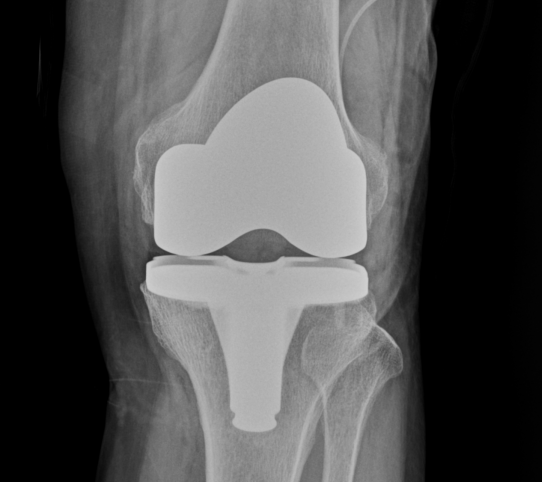

Prostalac은 감염된 인공관절을 제거한 뒤 감염을 치료하면서 환자가 일정 부분 관절을 사용할 수 있도록 항생제 방출하며 감염 치료를 돕는 항생제 함유 관절스페이서를 뜻함.

2)통상적으로 2단계 인공관절 재치환술 시행 시 사용